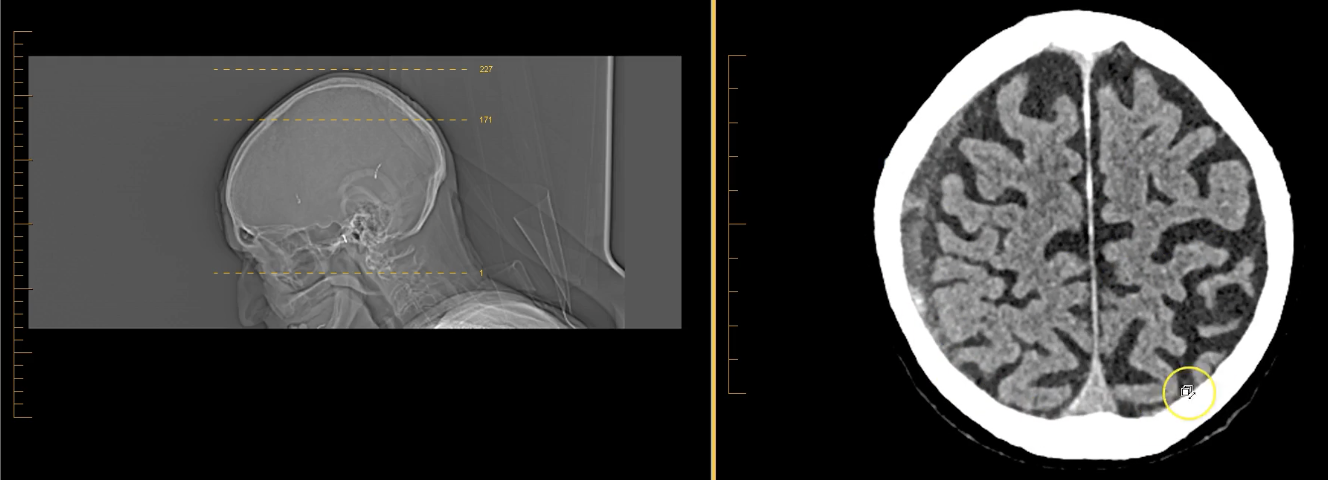

term image

thalamus